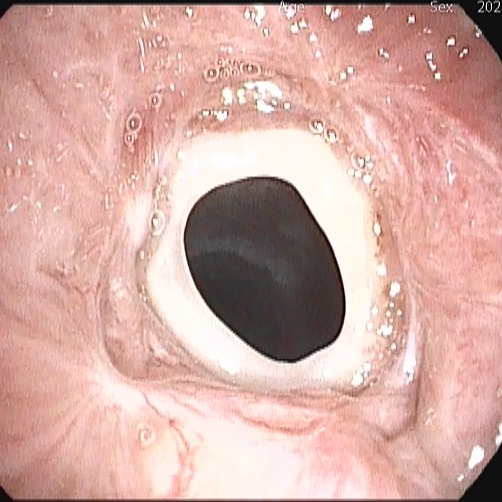

据了解,该患者为特殊瘢痕体质,因气管切开术后瘢痕过度生长,导致气管出现严重瘢痕增生与狭窄。此前,患者曾辗转多家医院,反复接受包括冷冻、电切、烧灼及气管支架置入在内的气管重塑术治疗,但效果均不理想,瘢痕仍反复增生,导致其呼吸受阻,生活质量受到严重影响。

患者气管出现严重瘢痕增生与狭窄

为寻求一线生机,患者在外院置入了硅酮支架并进行了缝合外固定。然而,由于术后反复剧烈咳嗽,外固定缝线不幸断裂,导致硅酮支架移位。移位的支架不仅未能解决狭窄问题,反而持续刺激气道,引发更剧烈的咳嗽并刺激瘢痕生长,形成恶性循环,使患者病情一度陷入困境。